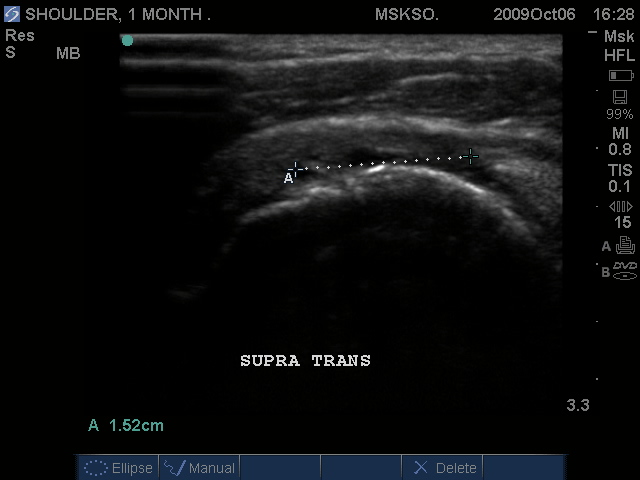

Supraspinatus tendon transverse over humeral head articular surface (articular surface changes in echotexture to hypoechoic)

"Cartilage Interface Sign" the hyperechoic rim over the hypoechoic articular cartilage is not usually seen unless a fluid layer is between the tendon and cartilage surface. When the tendon is resting normally over cartilage the interface is only hypoechoic.